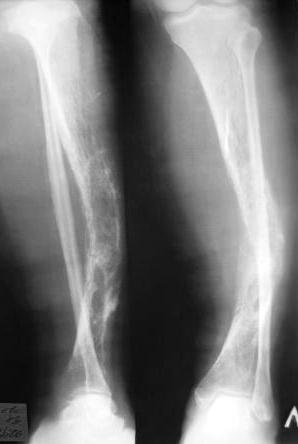

Фиброзная дисплазия?

Пациентка Ч. дата рождения 28.02.1962. Болеет на протяжении 3 лет, появились боли в левой голени, отеки голени, стопы. Обследования не проходила, лечения не получала.

15 сентября 2006 года – усиление болей.

Обследовалась в поликлинике с DS:

хронический гематогенный остеомиелит.

23.09.2006. травма – упала на левую нижнюю конечность – госпитализирована в ЦРБ, откуда направлена в областной онкологический диспансер.

В ООД обследование:

09.11.2006. операция: инсцизионная биопсия опухоли левой б/берцовой кости.

Взято 3 куска по 2.0 см.

Заключение гистолога: присланы скудные биоптаты из опухоли левой б/берцовой кости в виде мелких фрагментов размерами 0.2 х 0.5 см, с наличием костных фрагментов губчатого вида и мягкотканных кусочков. При исследовании: иррегулярные костные балки обычной архитектоники без атипии остеоида, лежат изолированно друг от друга, между ними зрелая клеточно-волокнистая фиброзная ткань. В прилежащей клетчатке очаги отложения солей кальция, мелкоочаговые кровоизлияния. Более всего можно думать о фиброзной дисплазии.

У нас обследование: гаммасцинтиграфия – очаги скопления препарата в левой б/берцовой кости, 8 ребре слева. Данных за б-нь Педжета нет.

Рентгенограммы:

- правая голень – варусная деформация диафиза б/берцовой кости.

После обсуждения пациентки к единому мнению по тактике лечения данной пациентки прийти не удалось. Может быть кто-то сможет поделиться своим опытом или мыслями по данному поводу?